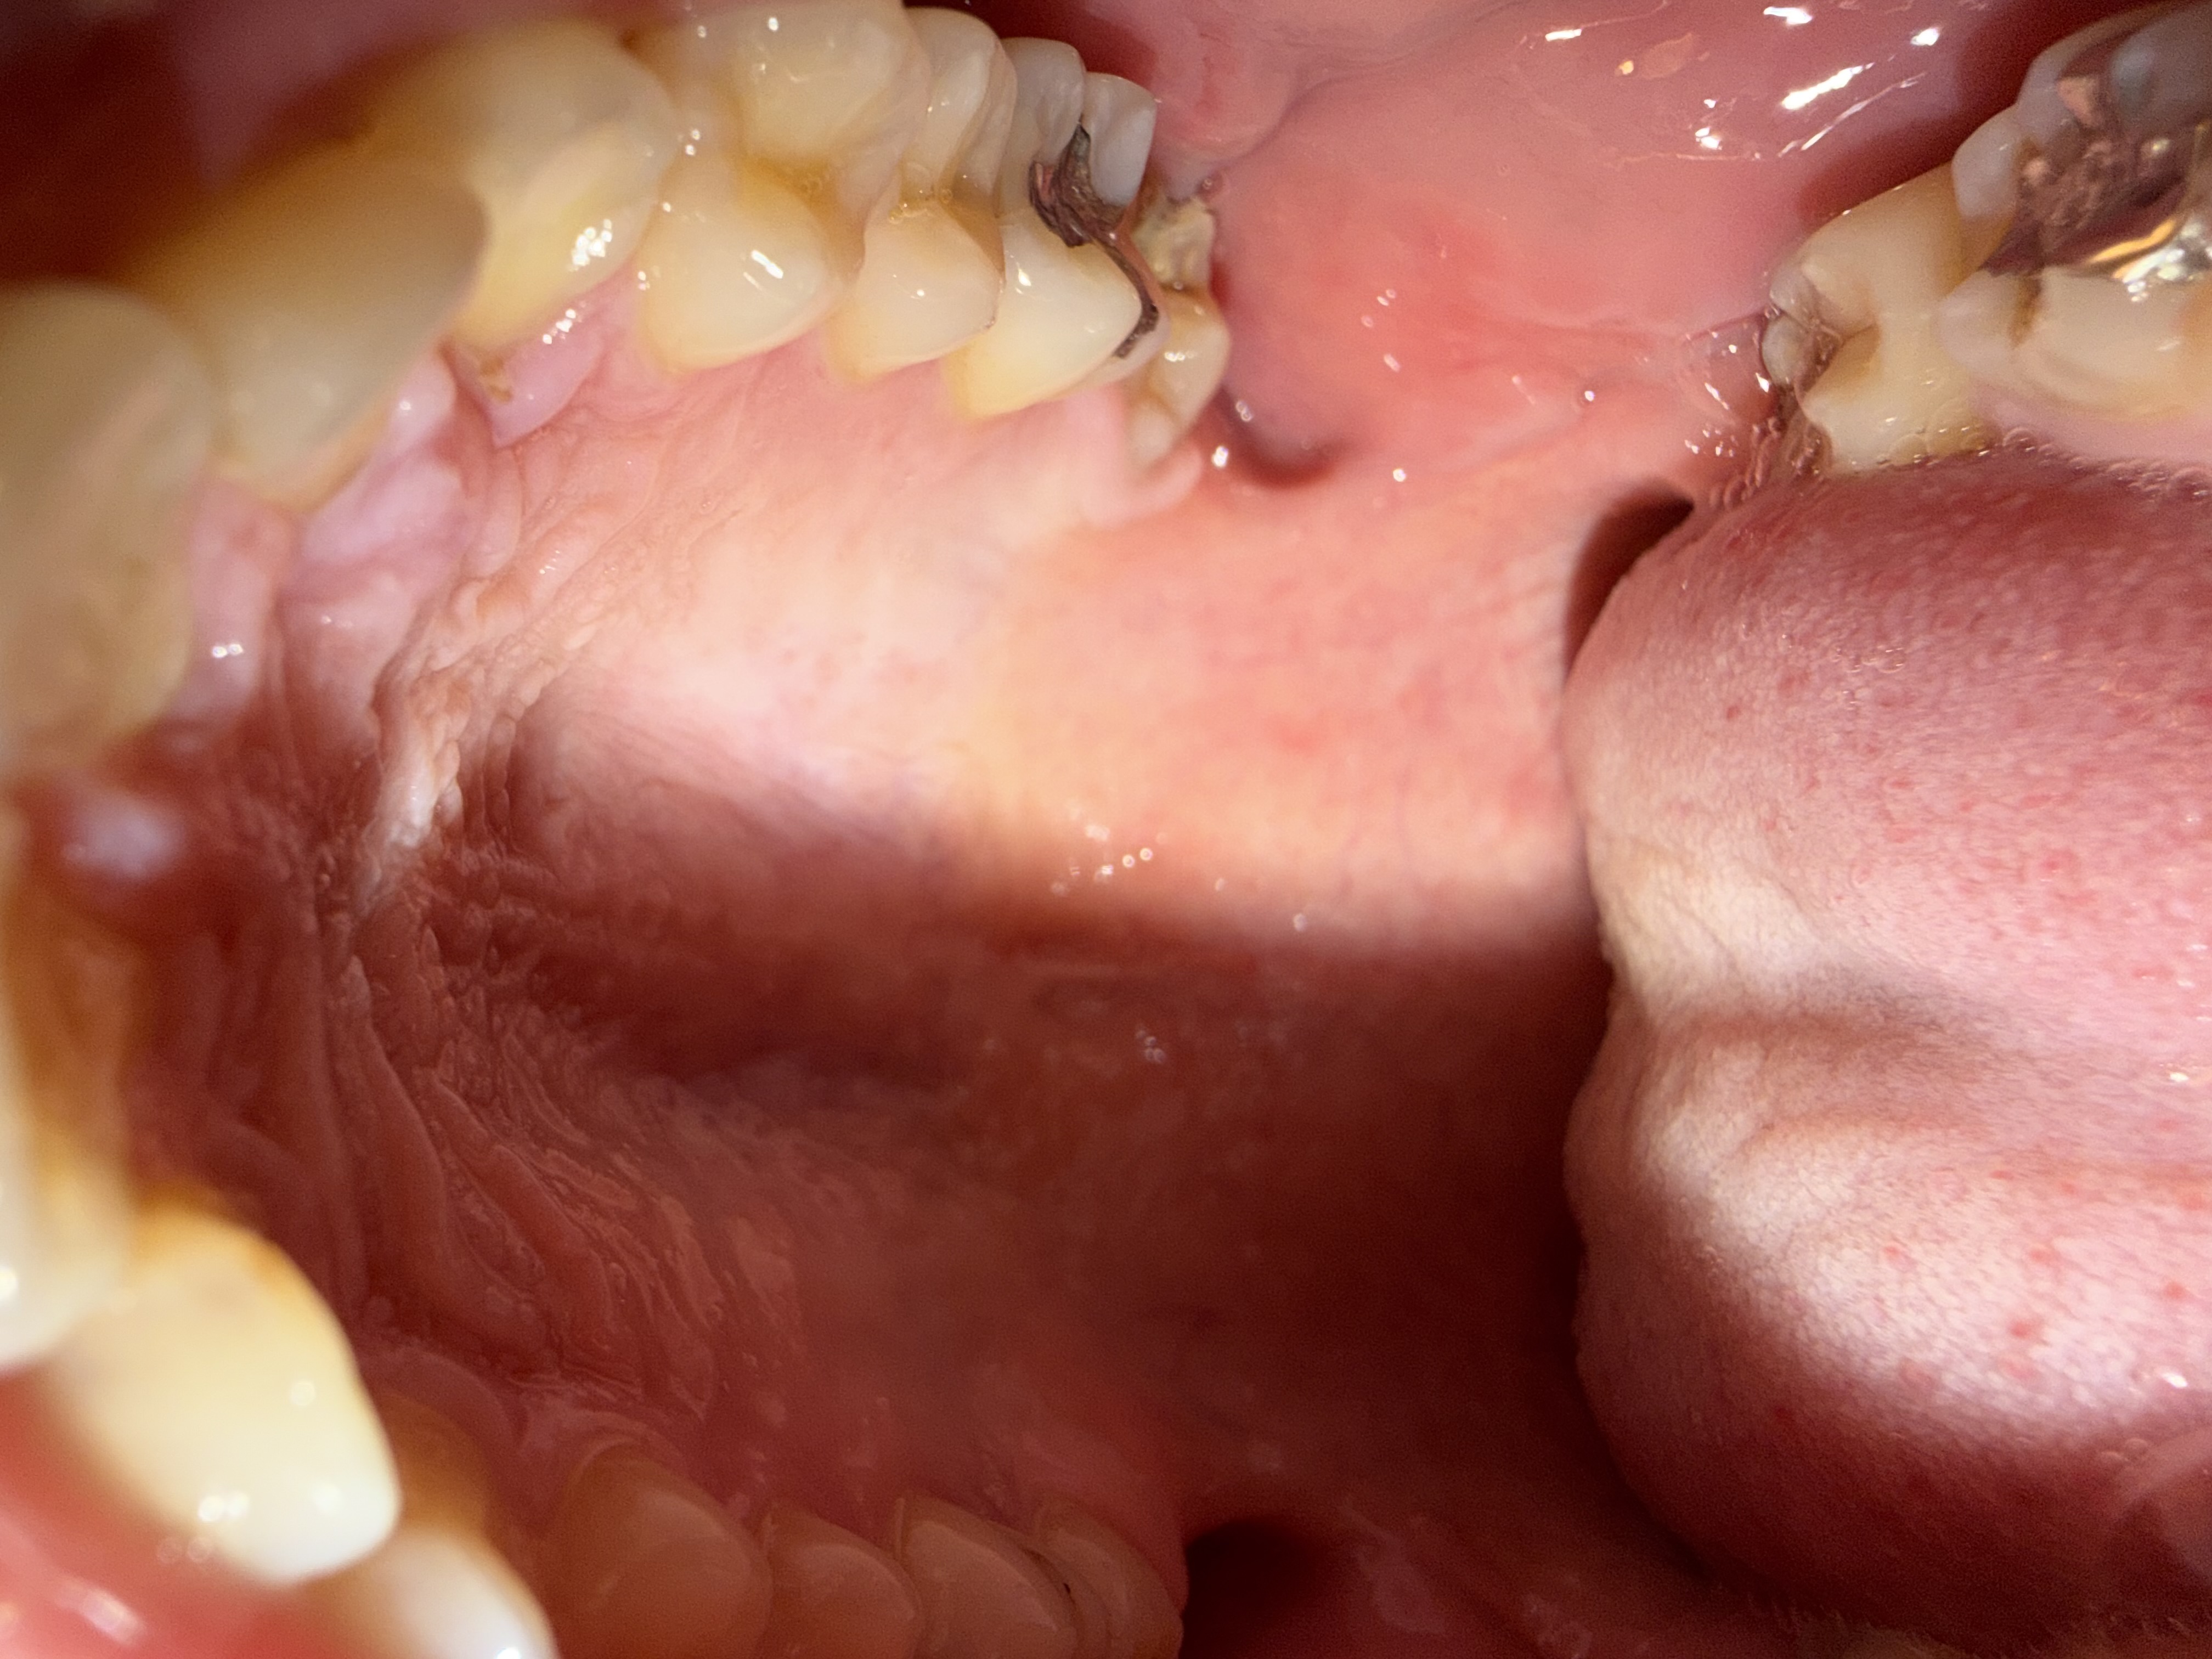

柔らかいものを食べていたら、奥歯が欠けてしまいました。